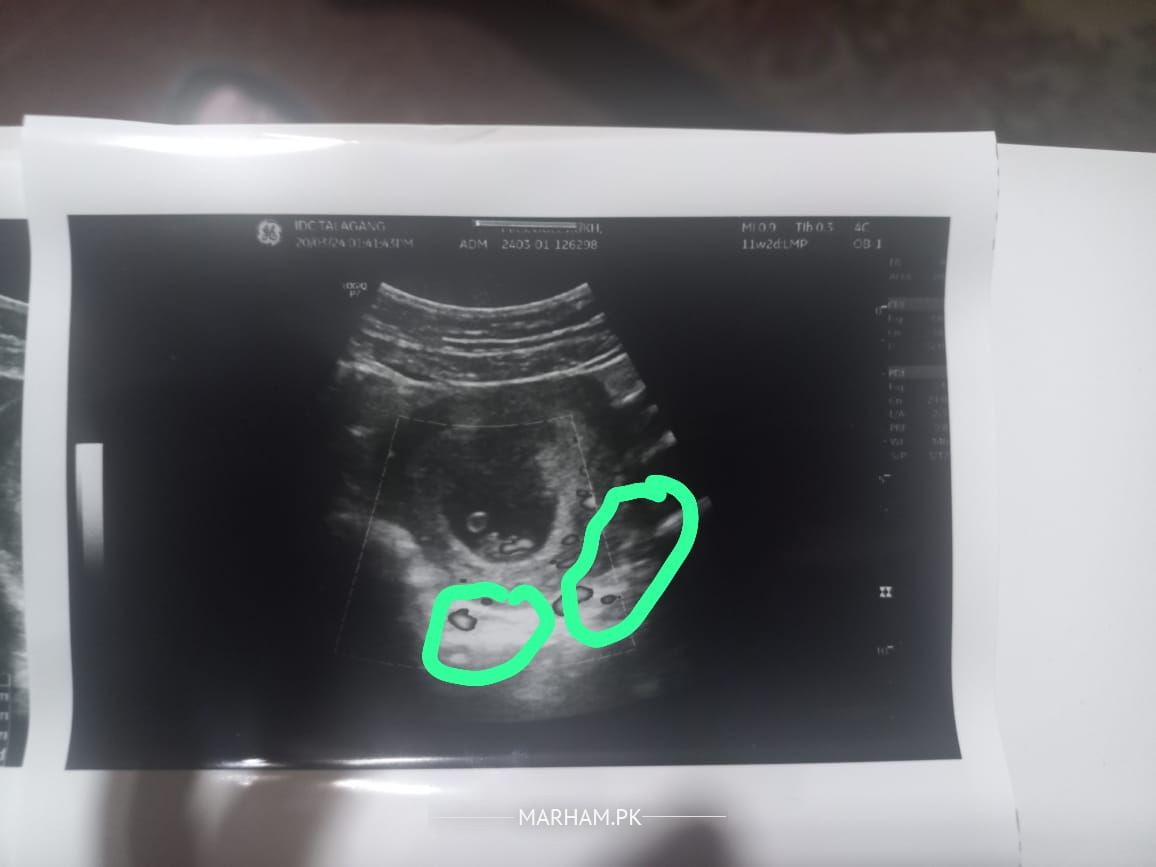

salam meri pregancy 8 week ki hai ultrasound mn jo green nishan k under hai wo kya hai

no need to worry your report is normal

gestational age 8 week +2 days ha

artifacts